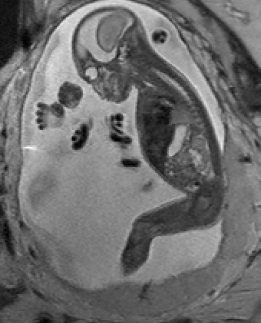

Reconstruction of Fetal Organs: Exemplary PVR and SVR reconstructions under motion introduced by kicking of the fetus are shown in Fig. 11. PVR reconstruction results show an improved visual appearance and less blurring in the region with severe motion artifacts (arrow). An example of a challenging clinical case with a kidney malformation in one of twin fetuses, is shown in Fig. 8. Our clinical partners confirmed that such complications are easier to examine and to quantify after PVR-based reconstruction.

Reconstruction of large-scale anatomy: MRI has also been shown to be very useful for the evaluation of the whole uterus and structures like the placenta. During both, normal and high-risk pregnancies, the whole uterine appearance and the condition of the placenta are considered to be an indicator for fetal health after birth [18]. Placental functions affect the birth weight as it controls the transmission of nutrients from the maternal to the fetal circulation [19]. However, the whole fetal body and secondary uterine parts can be inherently inconsistent. Different fetal body parts can move independently from the uterus. This makes the application of SVR and 2D-3D registration to the full uterus impossible in the presence of fetal motion and maternal respiration.

Besides, multiple births is a case where classical SVR pipelines based on preprocessing steps to identify consistent rigid regions will likely fail. The presence of multiple instances of the same fetal structure is usually not considered in previous methods. Therefore, a fully automatic motion correction method for the whole uterus, as it is presented in this paper, is very desirable and will enable the application of standard 3D image analysis techniques, e.g., [20, 21].